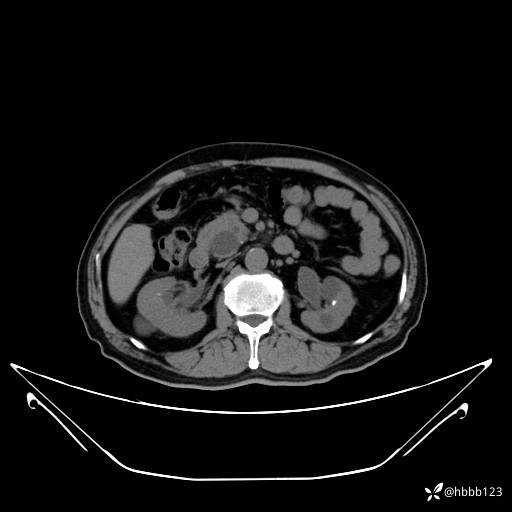

门诊完善上腹部CT平扫+增强扫描:

动脉期: